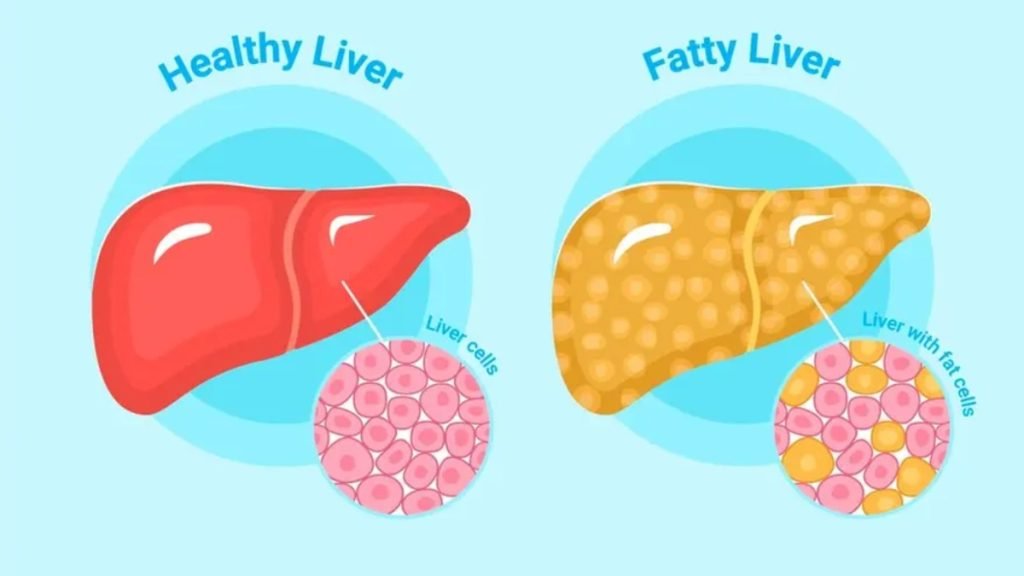

🧠 फैटी लिवर क्या होता है?

जब लिवर में जरूरत से ज्यादा फैट (वसा) जमा हो जाता है, तो इस स्थिति को फैटी लिवर कहा जाता है। यह दो प्रकार का होता है:

Alcoholic Fatty Liver – शराब के सेवन से

Non-Alcoholic Fatty Liver (NAFLD) – गलत खान-पान और लाइफस्टाइल से